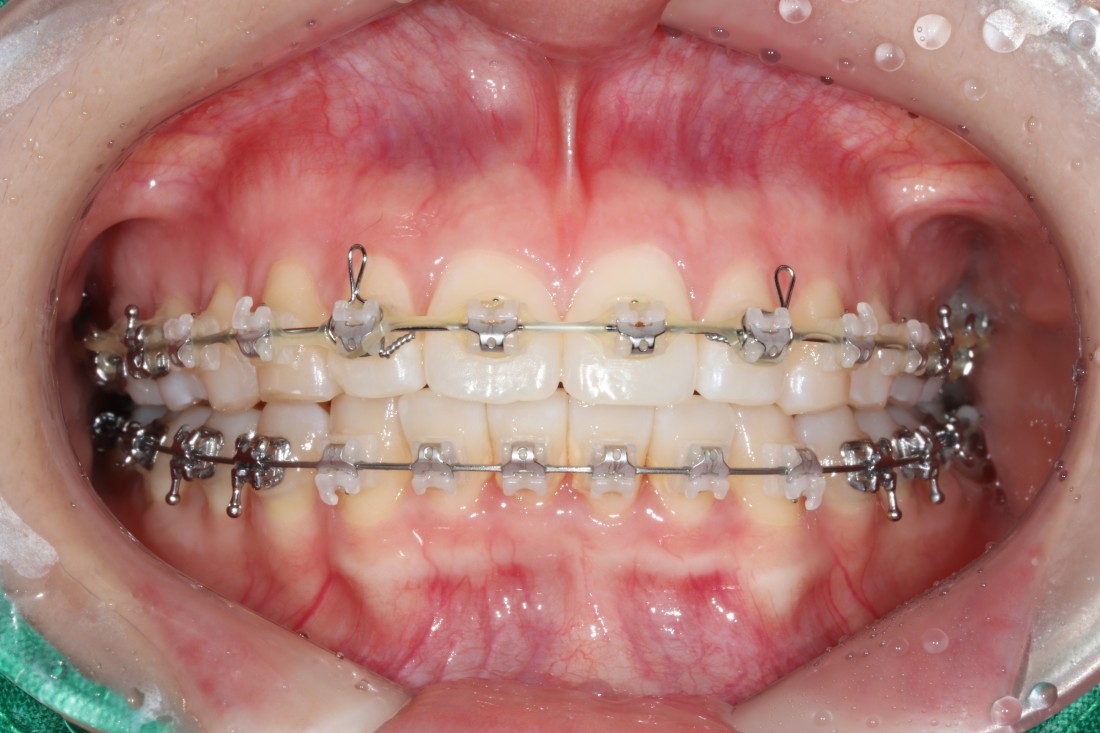

광주 교정치과

충치치료 + 치아교정 동시 케이스

광주 교정치과 추천하는 이유는

전문의 충치치료까지 동시에 가능하여

토탈 구강건강 관리를 받으실 수 있기 때문입니다.